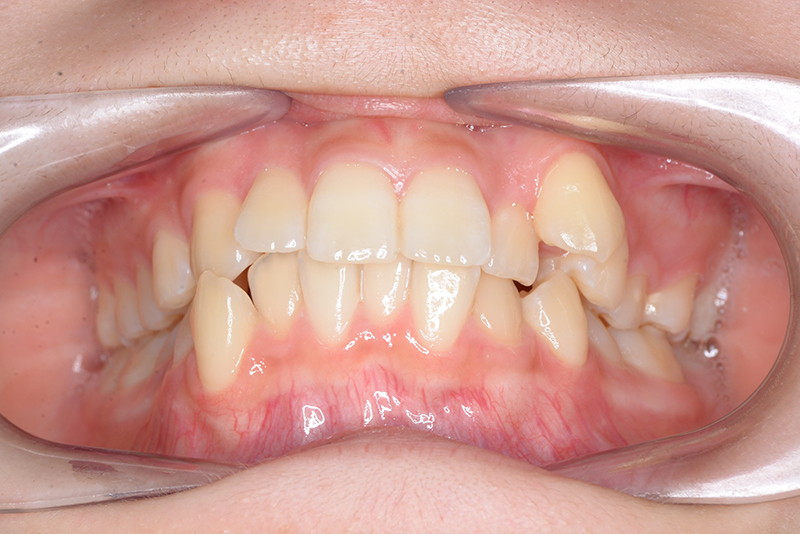

| 主訴 | 前歯のでこぼこ | 診断名 | アングルⅠ級叢生症例 | ||||

|---|---|---|---|---|---|---|---|

| 初診時年齢 | 15歳6ヵ月 | 性別 | 女 | 動的治療期間 | 23ヵ月 | ||

| 顔貌所見 | 正貌はほぼ左右対称、側貌はstraight typeで軽度に口唇閉鎖不全が認められた。 |

| 口腔内所見 | over jet 3.8mm、over bite 30mm、臼歯関係I級、上下顎前歯部に叢生が認められ、下顎正中は右側へ4.5mm偏位していた。左上5はCRの治療痕が認められた。 |

| 批評・予后 | 治療後において閉唇時の頤筋の過緊張の改善及び咬合の緊密化と歯根のパラレリングが認められ、良好な咬合が確立できたと思う。 現在は保定をしつつ下顎両側第三大臼歯抜歯の抜歯を検討している。 |